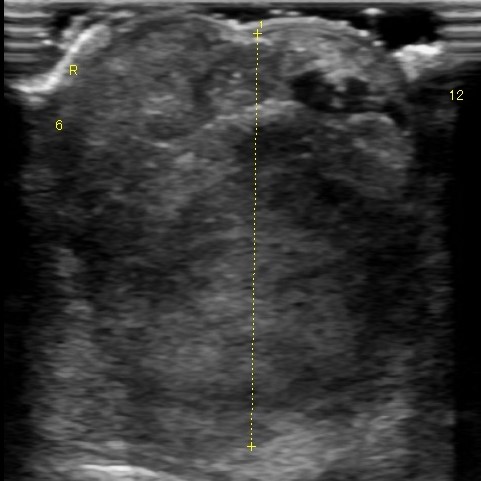

当院では各種眼科検査(涙液量検査・眼圧検査・細隙灯検査・眼底検査・眼超音波検査など)に対応し、一般外来および他の動物病院からの紹介も承っております。